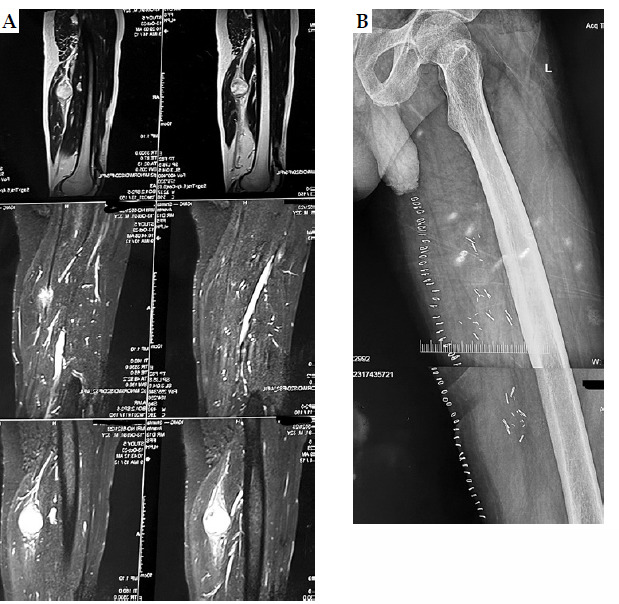

Material and methods: Seven patients with STS underwent conservative surgery and PHDRB between October 2020 and October 2023. PHDRB doses ranged from 3.0 to 3.5 Gy BID in 10 fractions, with or without subsequent EBRT, as indicated. EBRT was delivered in 4-5 weeks after surgical procedure at a dose of 45-50 Gy in 25 treatments, with daily dose of 1.8-2.0 Gy. Brachytherapy techniques and dosimetry guidelines were meticulously implemented to ensure optimal treatment delivery and minimize toxicity.